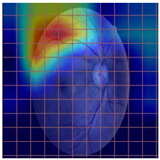

3.2. Models Explainability on the Test Set

| Original Image | VGG16 | ResNet-18 | DenseNet-121 |

|---|---|---|---|

![]() | ![]() | ![]() | ![]() |

| (a) | |||

| (b) | |||

| (c) | |||

| (d) | |||

| Model | Conformity with Normal Retinal Photos | Conformity with Abnormal Retinal Photos | Average Conformity |

| VGG16 | 0.2000 | 0.2414 | 0.2207 |

| ResNet-18 | 0.0294 | 0.0645 | 0.0469 |

| DenseNet-121 | 0.0385 | 0.0286 | 0.0336 |